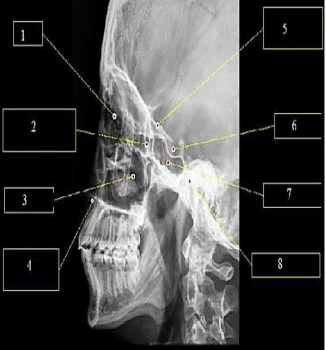

A imagem abaixo representa uma radiografia de crânio perfil.

A estrutura apontada pelo número 6 indica: